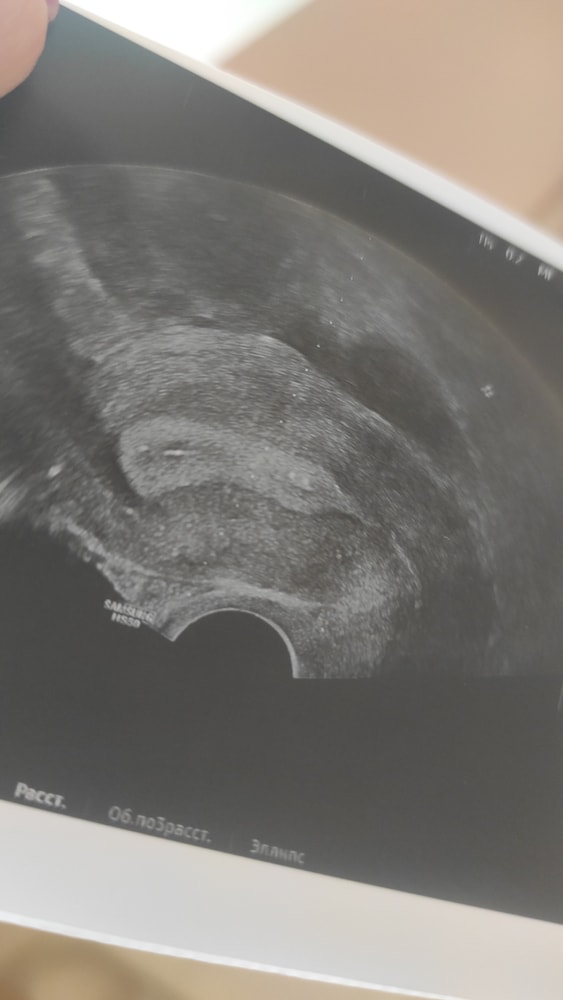

Дорогие девочки, смотрю на снимок после переноса и вижу что в отличие от первого раза где точечки на распечатанном УЗИ при подсадке были в середине матки сейчас они прям у самого низа матки где цервикальный канал

Мог ли доктор подсадить так низко , на след день дпп1 у меня выпали два крупных круглых кровяных сгустка в яичном белке круглой формы я в смятении могли ли просто выпасть эмбрионы и почему они подсажены так низко?

напишите фамилию врача и куда вам подсадил. Я расстроилась очень. Доктор отвечает что на фото просто не видно место подсадки но это не первый мой крио и мне всегда сажали выше в центр матки тут скажите честно ошибка врача?